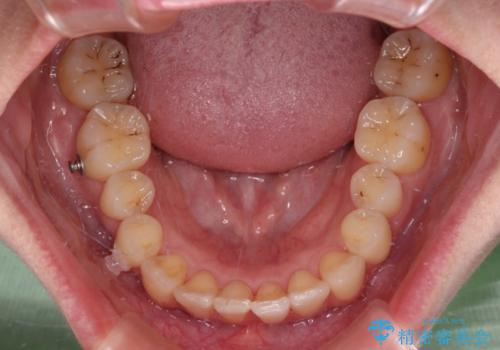

- 前歯のデコボコと強い咬みしめを気にして来院された患者様です。

インビザラインを用いて、前歯の叢生を解消するとともに、ディープバイトを改善していくこととしました。

海外へ転居する予定があったため、1日22時間以上の装着時間をしっかりと守っていただき、予定期間よりも早く、思っていた以上にきれいに仕上げることができました。